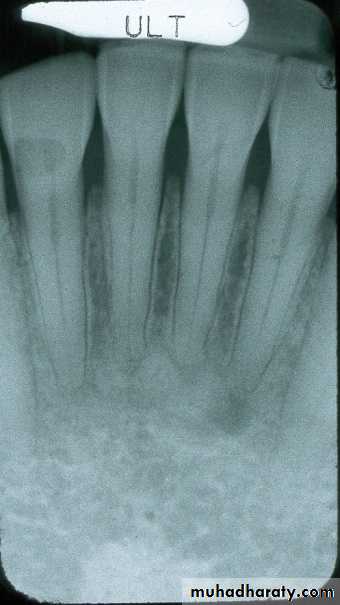

Mandibular Incisor

film centered on midline

film positioned away from teeth, pushing tongue back slightlyMandibular Canine

film centered on caninefilm positioned away from teeth, pushing tongue back slightly